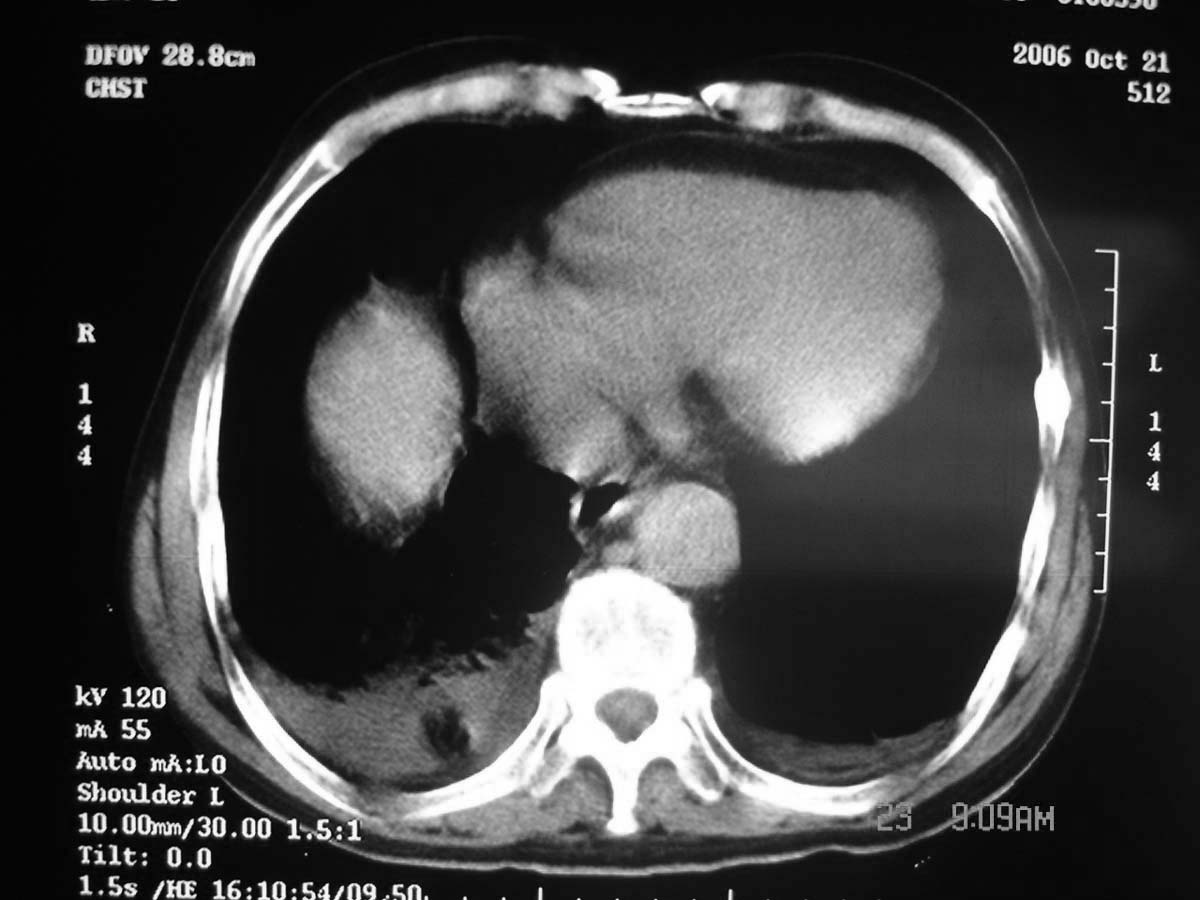

以下是引用守望可可西里在2006-11-23 14:33:00的发言:[br][br] 糖尿病病人很容易继发结核,病人又有双侧胸膜增厚、粘连、胸腔积液以及双上肺的斑片状、条索状影结核病灶影,以一元论考虑,右下肺病变首先考虑干酪性肺炎,可以正规抗炎治疗后复查,排除一般的肺炎。